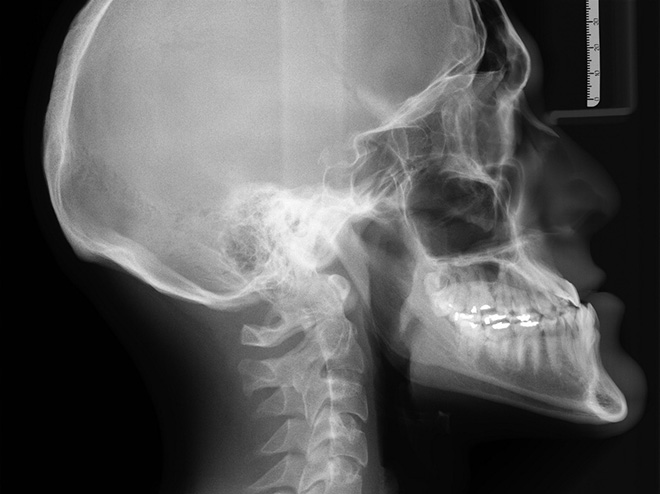

뢴트겐의 놀라운 발견으로 인류는 의학 분야의 큰 발전을 이룰 수 있었고, 의학뿐만 아니라 재료 연구나 여러 검사의 영역에서도 여전히 활발히 쓰이고 있습니다. 뢴트겐이 발견한 것은 바로 X선(X-ray), 병원에서 우리 몸의 안쪽을 들여다보아야 하거나 공항에서 짐 수색이 필요할 때 이 X선이 활용됩니다.

여기서 뢴트겐은 한 가지 아이디어를 떠올리게 되는데, 당시 사진건판이 발명되어 사진관에서 사진을 찍는 것이 유행이었습니다. 뢴트겐은 이 사진건판을 이용하여 새로운 빛을 활용해 감광 사진을 찍는 아이디어를 떠올렸습니다. 그 결과는 우리에게 너무나 잘 알려진 바로 그 사진에 담겨 있지요. 약혼녀의 손을 찍은 이 사진은 뢴트겐에게 새로운 빛이 존재한다는 명백한 증거가 되었고, 이 미지의 빛은 미지의 선이라는 의미로 X선(X-ray)이라고 부르게 되었습니다. 당시 뢴트겐의 X선 발견은 사회적으로 큰 충격이었는데, 사생활을 크게 침해할 수 있다는 걱정과 그에 관련한 광고까지 나왔을 만큼 사회문화적으로 불투명한 물질의 내부를 들여다볼 수 있다는 사실은 적잖은 충격이었습니다.

X선은 발견되자마자 많은 분야에서 활용되었는데요. 최초로 X선을 활용하여 절개 없이 골절을 진단하거나, 머리에 박힌 탄환을 확인하기도 하였습니다. 이전에는 신체 내부의 상태를 확인하기 위해 외과적 수술이 필수였는데, X선의 발견으로 절개하지 않고도 이를 확인할 수 있게 된 것입니다. 의학계에서는 페니실린의 발견에 버금가는 혹은 그 이상의 발견이었다고 할 수 있었지요.